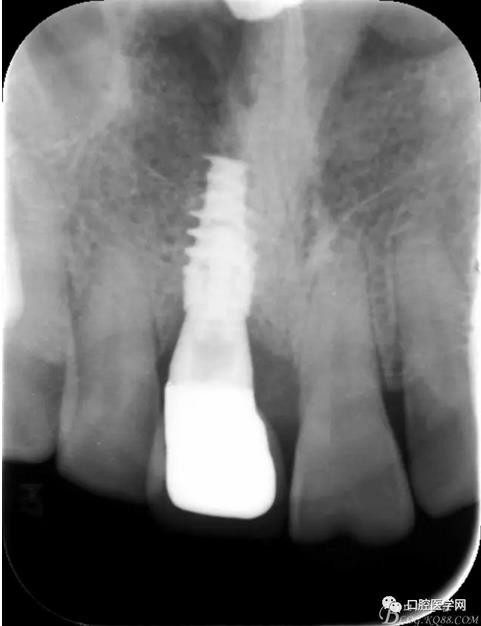

圖24 術(shù)后 X光片